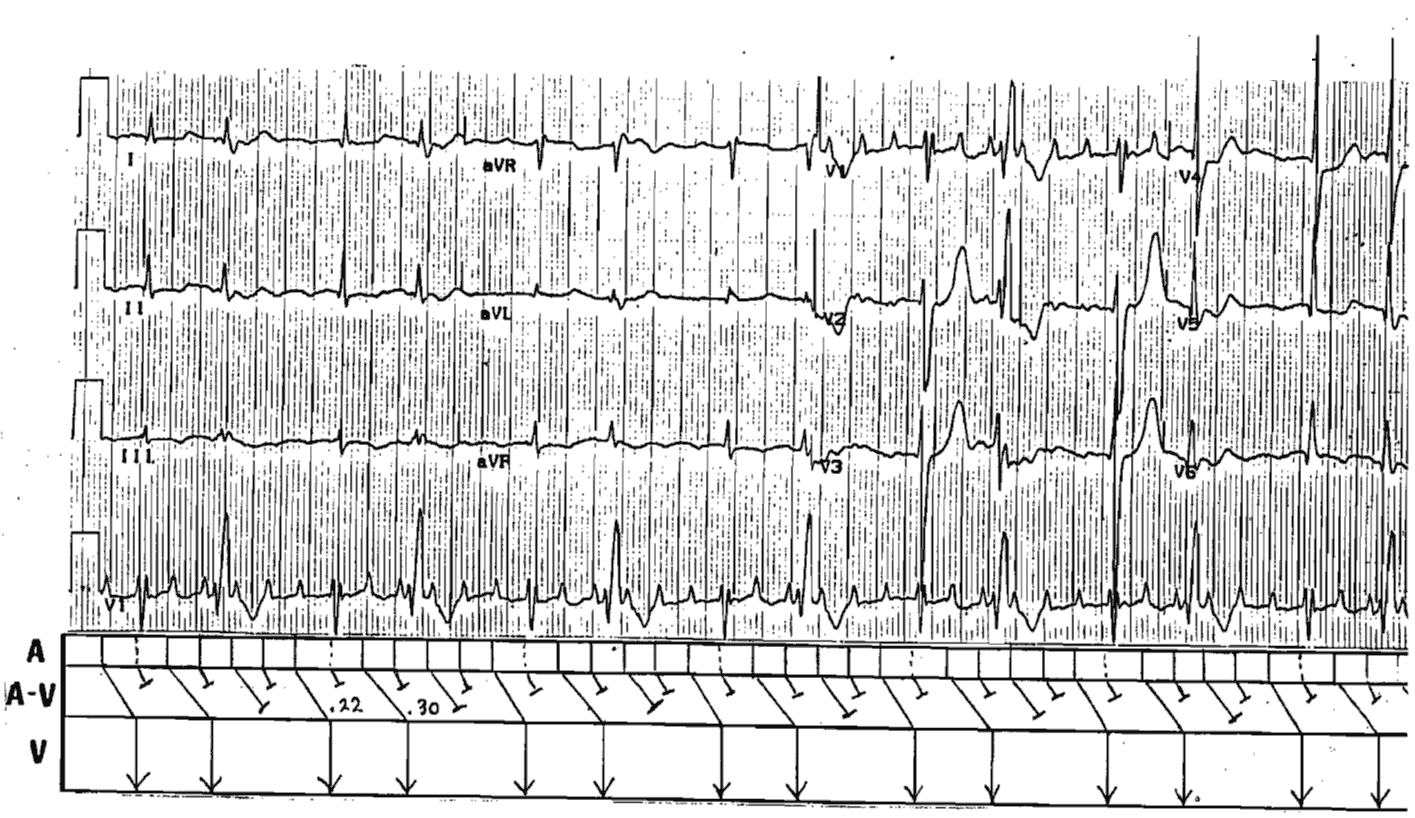

Interpretation

The ladder diagram depicts Atrial Flutter with 2:1 and 3:2 Wenckebach conduction.

The interesting aspect is the abnormal conduction with RBBB of the second transmitted impulse. The pause due to Wenckebach dropped beat, by the Ashman effect, sets the stage for the aberrant conduction.